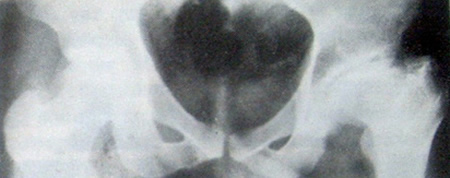

As alterações radiográficas incluem acentuada esclerose de um segmento importante da cabeça femoral que inclui a área de carga. O segmento esclerótico pode estar demarcado indefinidamente a partir do resto da cabeça por áreas irregulares de rarefação e esclerose: pode ter colapsado ou ter-se tornado impactado, resultando em incongruência articular (Fig. 13-27).

O prognostico da necrose avascular idiopática da cabeça femoral do adulto é de fato muito pobre em função da destruição irreparável da articulação.

Figura 13-27. Necrose avascular idiopática da cabeça femoral em um homem de 47 anos de idade que estava fazendo uso de adrenocorticóides por dois anos para tratamento de um distúrbio não relacionado. Note a esclerose de um grande segmento da cabeça femoral. A área convexa de apoio colapsou com a incongruência resultante das superficies articuIáveis. Áreas irregulares de reabsorção óssea podem ser vistas entre ou grande segmento esclerótico e ou resto da cabeça femoraI. O quadril deste homem está irremediavelmente danificado.